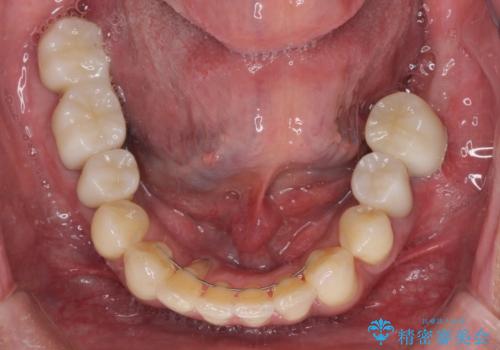

インプラント埋入後、手前のインプラント周りの丈夫な歯肉(角化歯肉)が失われてしまったため、角化歯肉の移植を行うこととなりました。

十分な角化歯肉が獲得でき、清掃性の高い環境が達成されました。